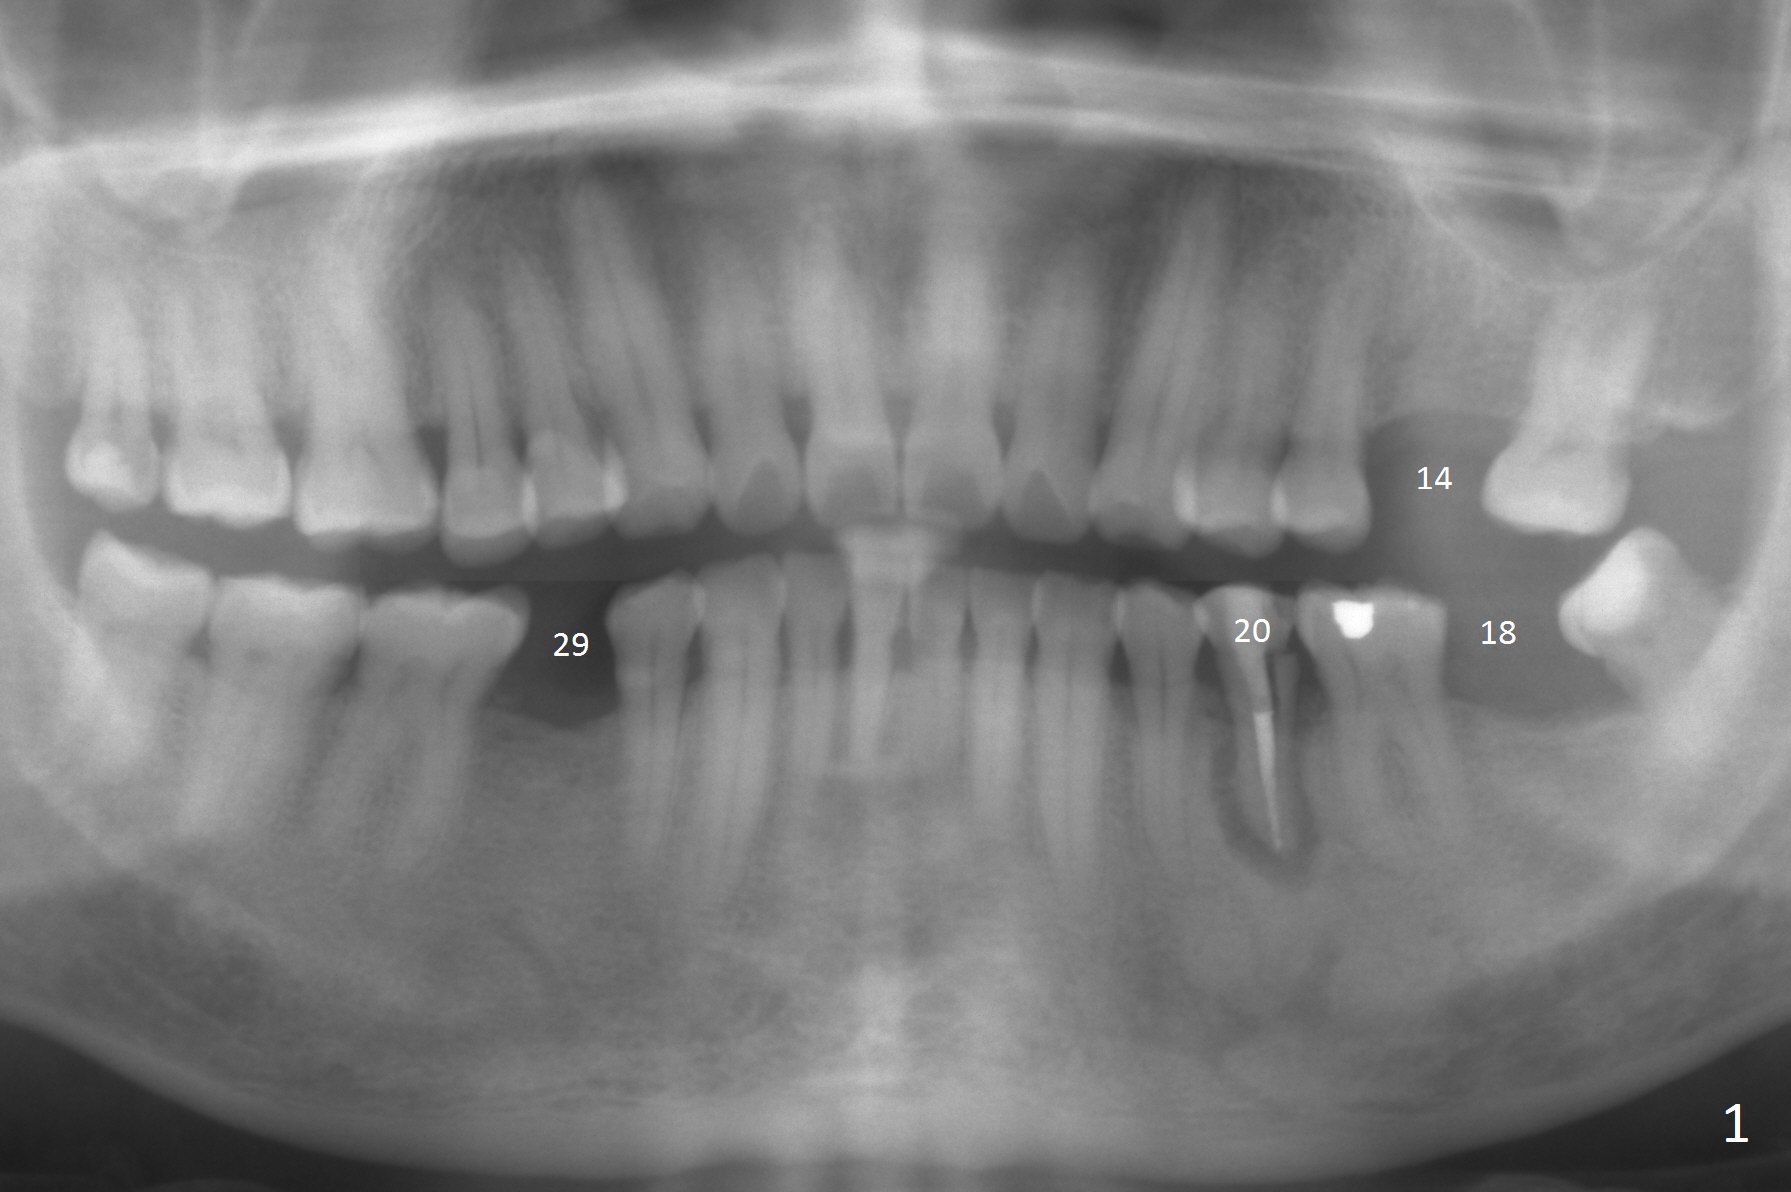

A 53-year-old man (probably bruxer, long roots) has 3 missing teeth (Fig.1 #14,18,29) and 1 fractured tooth (Fig.2 #20). The fractue is associated with deep buccal pockets. The buccal plate is most likely defective. After extraction (Metronidazole), start osteotomy lingual and mesial (Fig.3 red long arrow) to reduce damage to the Mental Loop (Fig.4 red dashed line). Damage to the Incisive Canal (yellow dashed line, the continuum of the Inferior Alveolar Canal after giving off the Mental Loop) is less significant. Since the defect is long, use the longest implant and place it deep. A long abutment (7 mm, green) with 5 mm cuff (pink) is required. To have sufficient buccal gap for bone graft and probably membrane, the smallest two-piece implant is necessary (3.8 mm).